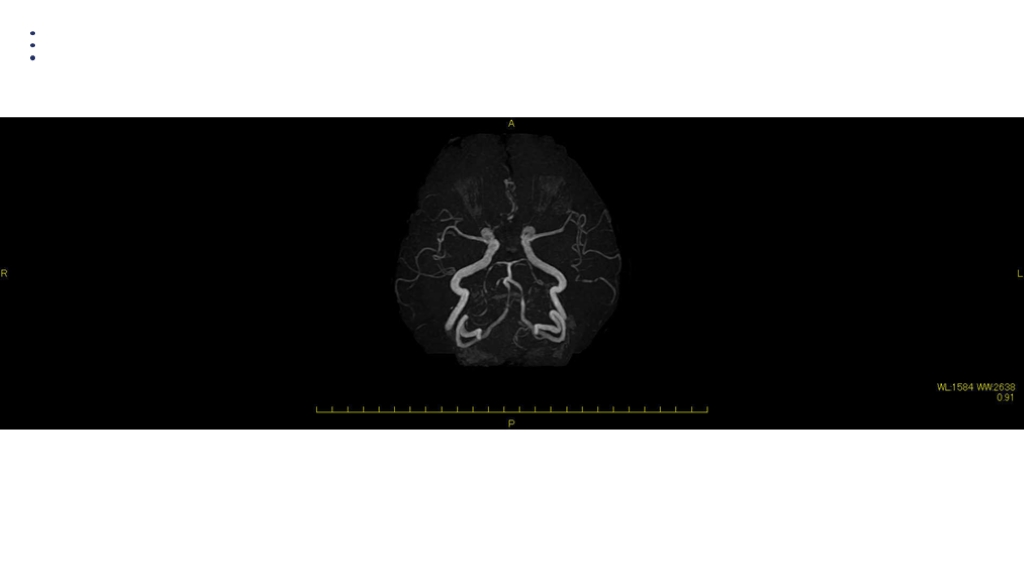

#35.

MRA DAY2